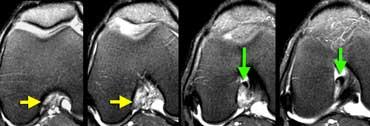

Hội chứng ma sát dải chậu chày

Vị trí ma sát bất thường thường gặp là giữa dải chậu chày và lồi cầu ngoài, hay xảy ra ở vận động viên đi bộ tốc độ cao, đạp xe và đôi khi ở người chạy bộ.

Khi túi hoạt dịch hình thành tại vị trí này, tình trạng này được gọi là ‘Hội chứng ma sát dải chậu chày’.

Hình bên trái là một vận động viên đi bộ tốc độ cao với triệu chứng đau mặt ngoài gối.

Bình thường phải có mô mỡ giữa dải chậu chày và lồi cầu ngoài, nhưng trong trường hợp này mô mỡ không còn hiện diện.

Hội chứng ma sát dải chậu chày: Dịch trong túi hoạt dịch thấy được giữa dải chậu chày và xương đùi (mũi tên vàng). Dịch khớp dừng lại tại các mũi tên đỏ.

Cùng bệnh nhân trên. Trên các lát cắt axial, có thể thấy dịch trong túi hoạt dịch nằm giữa dải chậu chày và xương đùi bên dưới.

Đôi khi cần phân biệt dịch tại vị trí này với dịch khớp.

Cần xem xét toàn bộ các lát cắt hình ảnh.

Trong trường hợp này, dịch khớp dừng lại tại các mũi tên đỏ.